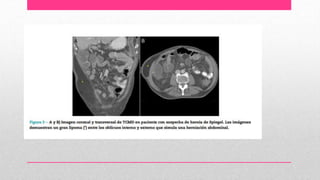

Hernia de spiegel

• herniación de contenido abdominal a través de la línea semilunar y

borde externo del músculo recto,

• Es poco frecuente y difícil de diagnosticar

• Mas frecuente en mujeres

• La fascia de Spieghel consiste en las aponeurosis fusionadas de los

músculos oblicuo menor y transverso del abdomen, entre el vientre

de estos músculos hacia afuera y el músculo recto en la línea media.

• son más comunes en el área comprendida entre el ombligo y la línea

que una la espina iliaca anterosuperior abajo de la línea arqueada y

arriba de los vasos epigástricos inferiores.